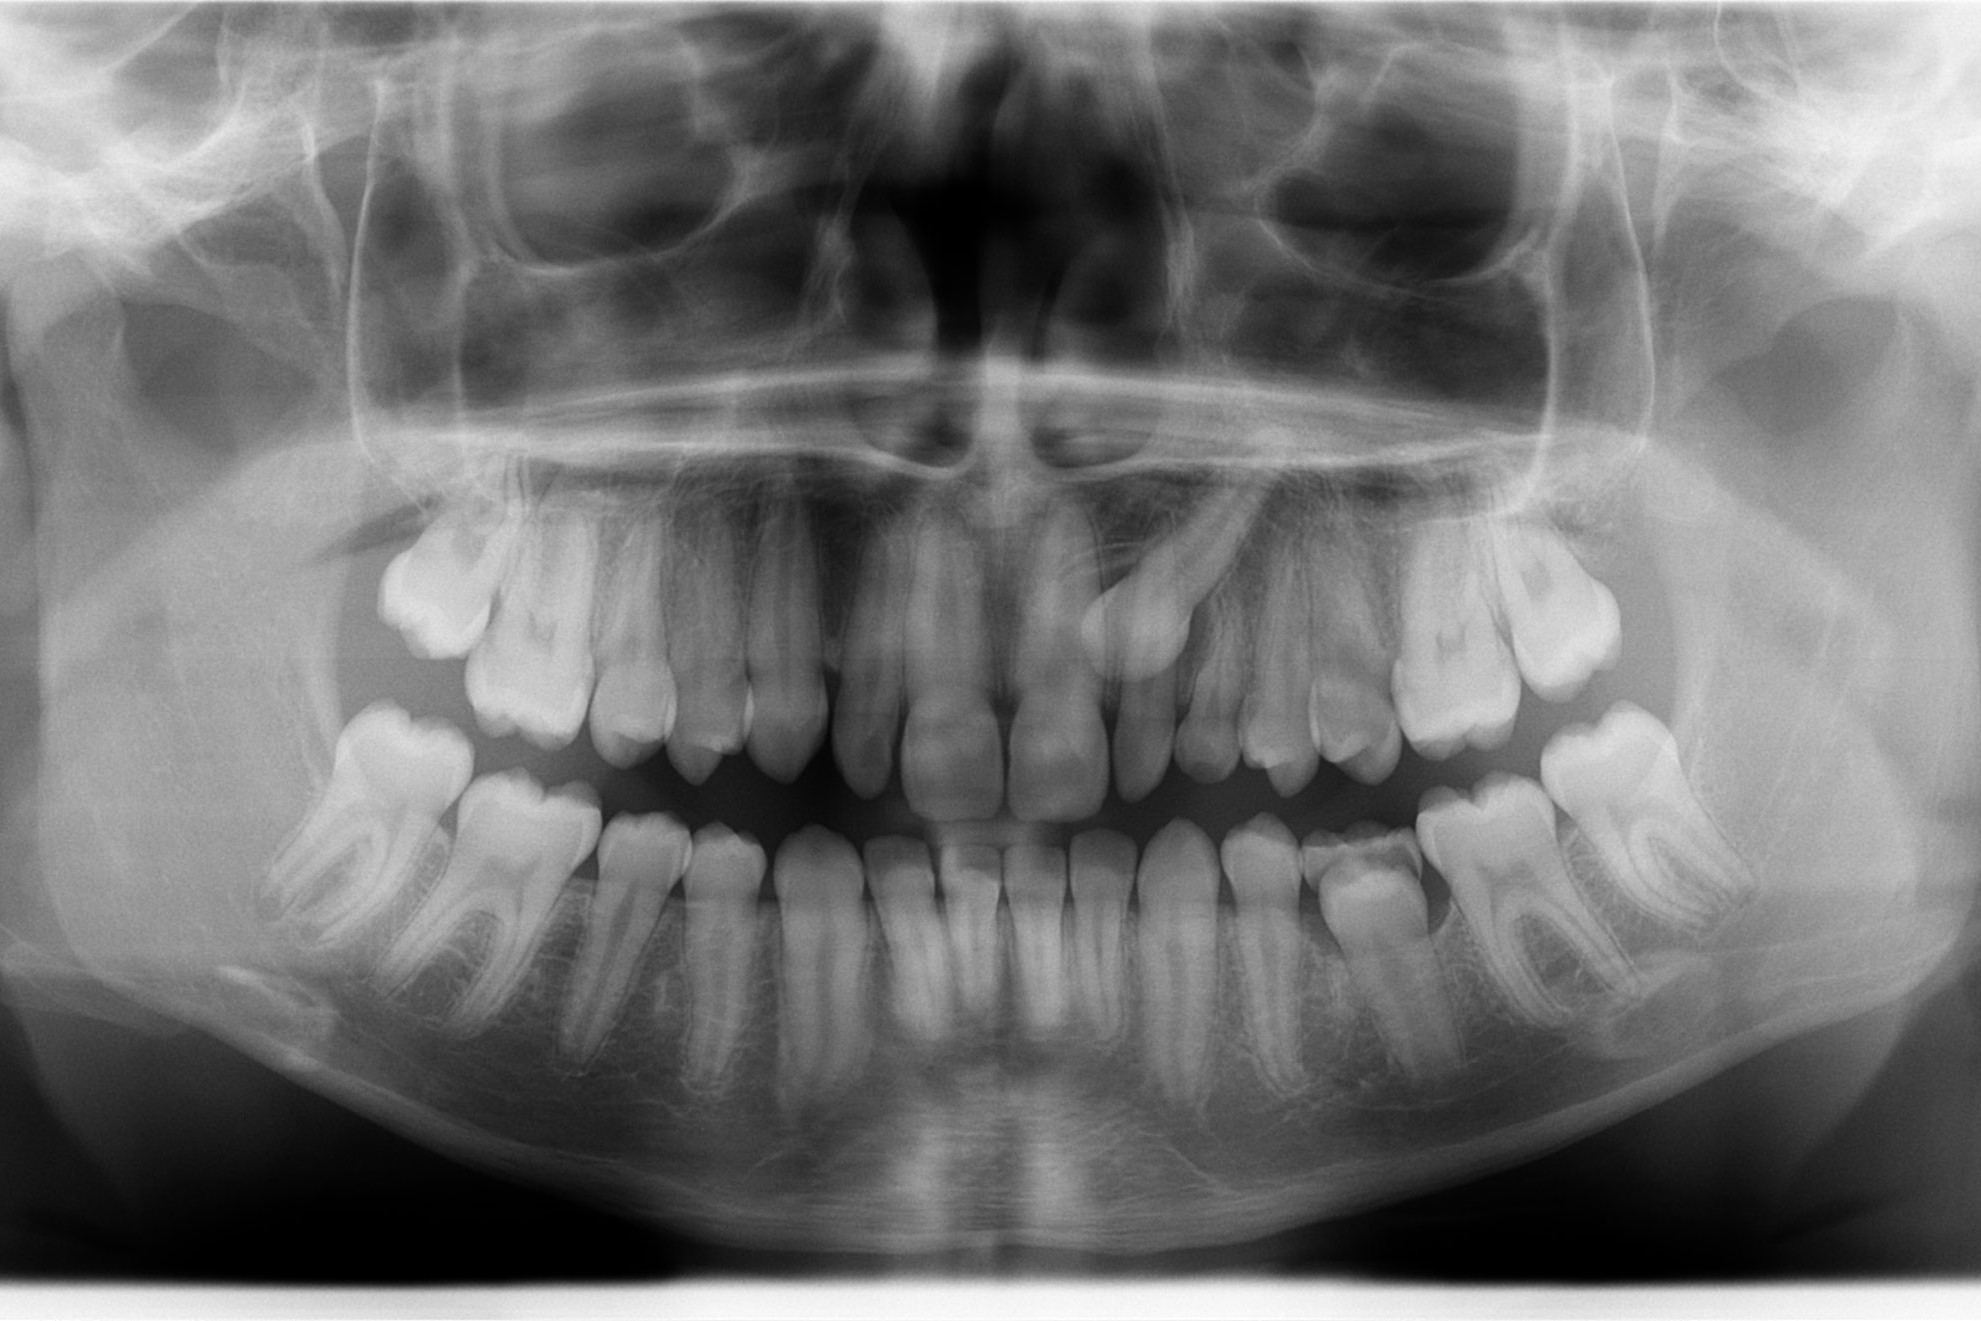

IMPLANTOLOGIA

Il tuo miglior investimento.

- Per sostituire uno o più denti

- Anche con innesti ossei o rialzo di seno mascellare

PARODONTOLOGIA

Per la tua salute orale ma non solo.

La malattia parodontale, infatti, ti espone maggiormente al rischio di malattie cardiovascolari, diabete, complicanze in gravidanza.